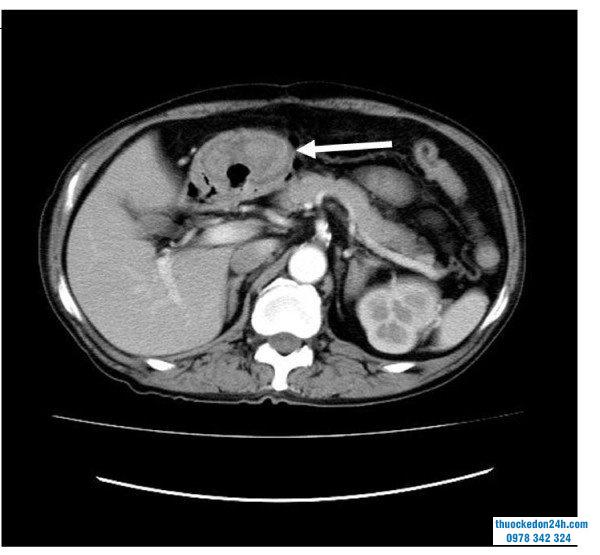

Tất cả các GIST đều có khả năng ác tính với mức độ hung hăng sinh học khác nhau. Chụp cắt lớp vi tính có cản quang (CT) là phương thức hình ảnh được lựa chọn để chẩn đoán trước phẫu thuật, phân giai đoạn, cũng như theo dõi hậu phẫu và đánh giá đáp ứng điều trị ở bệnh nhân GISTs.

Đánh giá chính xác nguy cơ ác tính và kết quả trong GISTs chủ yếu dựa trên kích thước khối u, vị trí (khối u mô đệm dạ dày so với khối u mô đệm ngoài dạ dày) và số lượng phân bào thu được từ các mẫu cắt bỏ. Các yếu tố này được kết hợp trong các tiêu chí của Viện Y tế Quốc gia 2008, đã phân loại GISTs thành bốn loại nguy cơ: rất thấp, thấp, trung bình và nguy cơ cao khối u. Tuy nhiên, trong thực hành lâm sàng, sự phân tầng nguy cơ có thể bị hạn chế bằng cách đánh giá số lượng phân bào ở những bệnh nhân được điều trị bằng liệu pháp bổ trợ mới, hoặc bằng cách đánh giá các mẫu sinh thiết không thể đại diện cho toàn bộ khối u. Do đó, một số nghiên cứu đã cố gắng dự đoán phân tầng nguy cơ dựa trên hình ảnh CT trước phẫu thuật. Các đặc điểm CT như kích thước, mô hình tăng trưởng hoặc các mạch nuôi mở rộng có liên quan đến các khối u nguy cơ cao. Tuy nhiên, phân tầng rủi ro bằng cách sử dụng đánh giá hình ảnh định tính bị ảnh hưởng bởi trải nghiệm của độc giả, định nghĩa không đồng nhất của các đặc điểm hình ảnh và đánh giá chủ quan với khả năng tái tạo dưới mức tối ưu của các đặc điểm định tính

Dự đoán phân tầng u mô đệm đường tiêu hóa qua ảnh CT